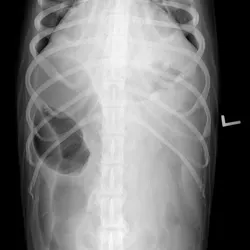

Abdominal radiographs (See Figure 1 above, right lateral; See Figure 2 below, ventrodorsal) showing severe gas distention of the colon (C) with displacement right of midline; there is also fluid and gas distention of the small intestines (SM). When radiographically assessing the intestinal tract, it is important to differentiate colon from small intestine. In this case, colonic torsion was suspected because of the segment of extreme dilation and lack of identification of normal colon.

Results of CBC and serum biochemistry profile were unremarkable. Abdomi­nal radiographs (See Figures 1 and 2) showed a severely gas-distended intestinal segment in the cranial to middle abdomen; other loops of bowel were mildly distended. The colon was not identified in its normal location. Intestinal obstruction from intestinal torsion, possible foreign body, or intussusception was suspected.